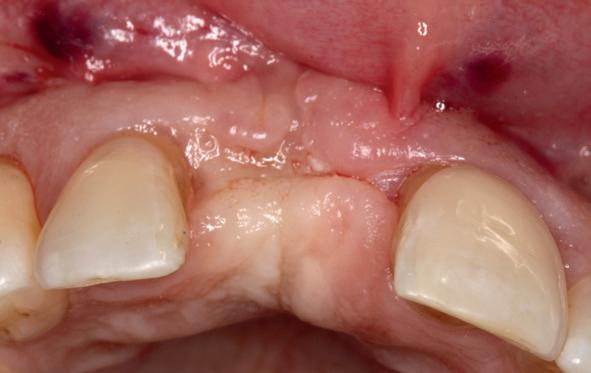

Implantologische behandelingen in het esthetische front vragen meer dan technische vaardigheid alleen. Ze vragen om overzicht, timing, vertrouwen en een team dat als vanzelf samenwerkt onder druk. Juist bij complexe casussen, waarin angst, infectie en hoge esthetische verwachtingen samenkomen, wordt zichtbaar hoe bepalend de rol van de tandartsassistent is.

Deze casus beschrijft een uitgebreide immediate implantaatbehandeling bij een patiënt die door meerdere collega’s werd geweigerd. Niet omdat de mogelijkheden ontbraken, maar omdat de complexiteit vroeg om een perfect afgestemde samenwerking. Het verhaal laat zien hoe de assistent in zo’n traject veel meer is dan een uitvoerende kracht of “mal”, maar een dynamische surgical guide die het proces mede stuurt, bewaakt en mogelijk maakt.De patiënt: wanneer alles samenkomt

Ze kwam binnen op een dinsdagochtend, iets voor achten. Een vrouw van begin zeventig, met een zachte stem en ogen die meer vertelden dan haar woorden. Ze vertelde dat ze een eigen B&B had en dat ze zich nauwelijks kon voorstellen gasten te ontvangen zonder tanden. Op dit moment kon ze echter nauwelijks lachen. “Het doet pijn… en het ruikt soms ook niet goed,” zei ze bijna verontschuldigend. Haar oude bovenbrug, die ze al meer dan twintig jaar droeg, was langzaam maar zeker ingestort. Er was sprake van cariës onder meerdere pijlers, pusafvloed,

chronische ontsteking en een brug die mobiel was en elke beet pijnlijk maakte. Ze had inmiddels meerdere tandartsen bezocht. Drie hadden haar geweigerd. Te complex. Te veel wensen. Te onvoorspelbaar.

De kern van haar vraag was eenvoudig en tegelijkertijd uitdagend: Is het mogelijk om mijn huidige brug te dupliceren en een nieuwe brug te vervaardigen met minder complicaties?

De basis van een complexe beslissing

Mijn behandelplan begint altijd met een uitgebreid klinisch onderzoek. Dat omvat een medische anamnese, intra- en extra-orale camerafoto’s en uitgebreid verwachtingsmanagement. In deze fase is mijn assistent vooral bezig met het zorgvuldig vastleggen van alle gegevens. Juist dat nauwkeurig documenteren zorgt voor rust in de behandelkamer. Minstens zo belangrijk is het luisteren naar de patiënt. Niet alleen naar de klachten, maar naar het

1. Extra-orale foto (lachlijn).

2. Beoordeling van zacht weefsel en botcontour.

3. Reflectiefoto – beoordeling van occlusievlakken en tandboog.

4. Pre-chirurgische OPG.

levensverhaal en de mens achter de brug. Begrijpen wat deze behandeling voor iemand betekent, is cruciaal voor het uiteindelijke succes.

Na het klinische onderzoek volgde het röntgenologisch traject. De CBCT liet precies zien wat we al vreesden: een front waarin het bot onregelmatig was, duidelijke radiolucenties rond de pijlers en een infectiegebied dat zich onder vrijwel de gehele brug had verspreid. Tegelijkertijd was er ook potentie. Net voldoende botstructuur om immediate implantaatplaatsing te overwegen, mits alles perfect gepland zou worden.